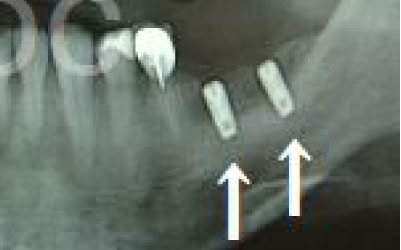

CTでは、骨や歯の状態を3Dで確認でき、正確な距離の測定も行えます。

骨の厚さや傾き、神経の位置などを事前にしっかりと測定することで、安全にインプラントを行うことができます。

骨が薄い場合、そのままインプラントを行うのはお勧めできません。

ただし、事前に骨を増やす治療を行ったり、インプラントと同時に骨を増やす治療を行えば、インプラントは可能です。

インプラント治療では、顎の骨内を通る神経を傷つけるリスクがあります。

ただし、事前にCTで三次元的に神経との距離を測り、治療計画を慎重に立てれば、心配することはありません。